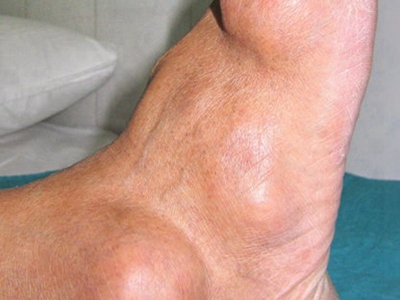

痛风病程较长,常反复发作而迁延不愈形成痛风石,是痛风的特征性临床表现,常见于指关节、第一跖趾关节、耳廓等处。外观为隆起、大小不一的不规则的黄白色赘生物,表面菲薄,破溃后排出白色粉状或糊状尿酸盐结晶物,经久不愈,但较少继发感染。部分患者伴有肾结石及肾脏病变。